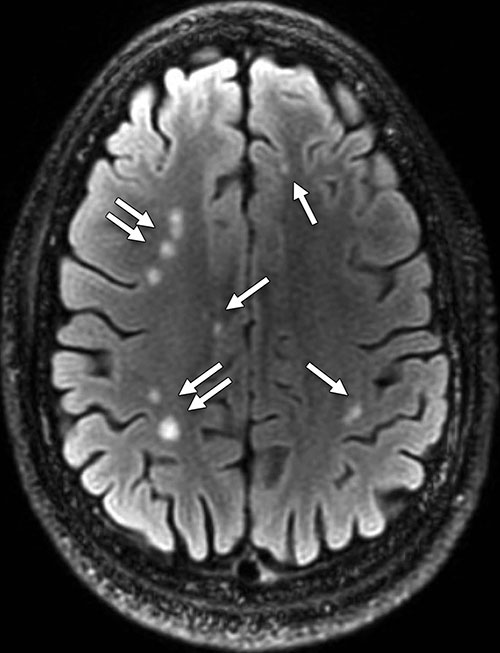

The participants were diagnosed with predominantly chronic (mean, 1,381 days; median, 888 days after injury) and mild (92 percent [768 of 834]) TBI. Of these participants, 84.2 percent (688 of 817) reported one or more blast-related incident and 63.0 percent (515 of 817) reported loss of consciousness at the time of injury. The presence of white matter T2-weighted hyper-intense areas was the most common pathologic finding, observed in 51.8 percent (432 of 834; OR, 1.75) of TBI participants. Cerebral microhemorrhages were observed in a small percentage of participants (7.2 percent [60 of 834]; OR, 6.64) and showed increased incidence with TBI severity (P < .001, moderate and severe vs. mild). T2-weighted hyper-intense areas and microhemorrhages did not collocate by visual inspection. Pituitary abnormalities were identified in a large proportion (29.0 percent [242 of 834]; OR, 16.8) of TBI participants.